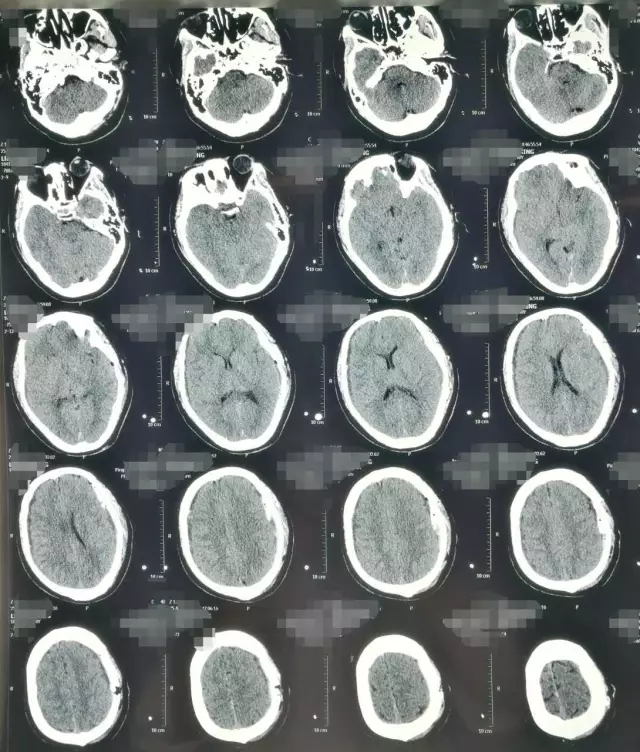

患者,男,40岁;因不明原因反复头痛并加重2月,于2017年4月21日当地医院头颅CT、MRI提示:双侧额颞顶部慢性硬膜下血肿收住院(图1)。并于4月24日行“左侧慢性硬膜下血肿钻孔引流术”。术后患者卧床、静脉补液,头痛症状有所缓解。复查头颅CT显示左侧血肿较前减少,但右侧稍增大(图2)。

图1. 第一次术前CT及MRI显示双侧慢性硬膜下血肿,中线稍右偏。